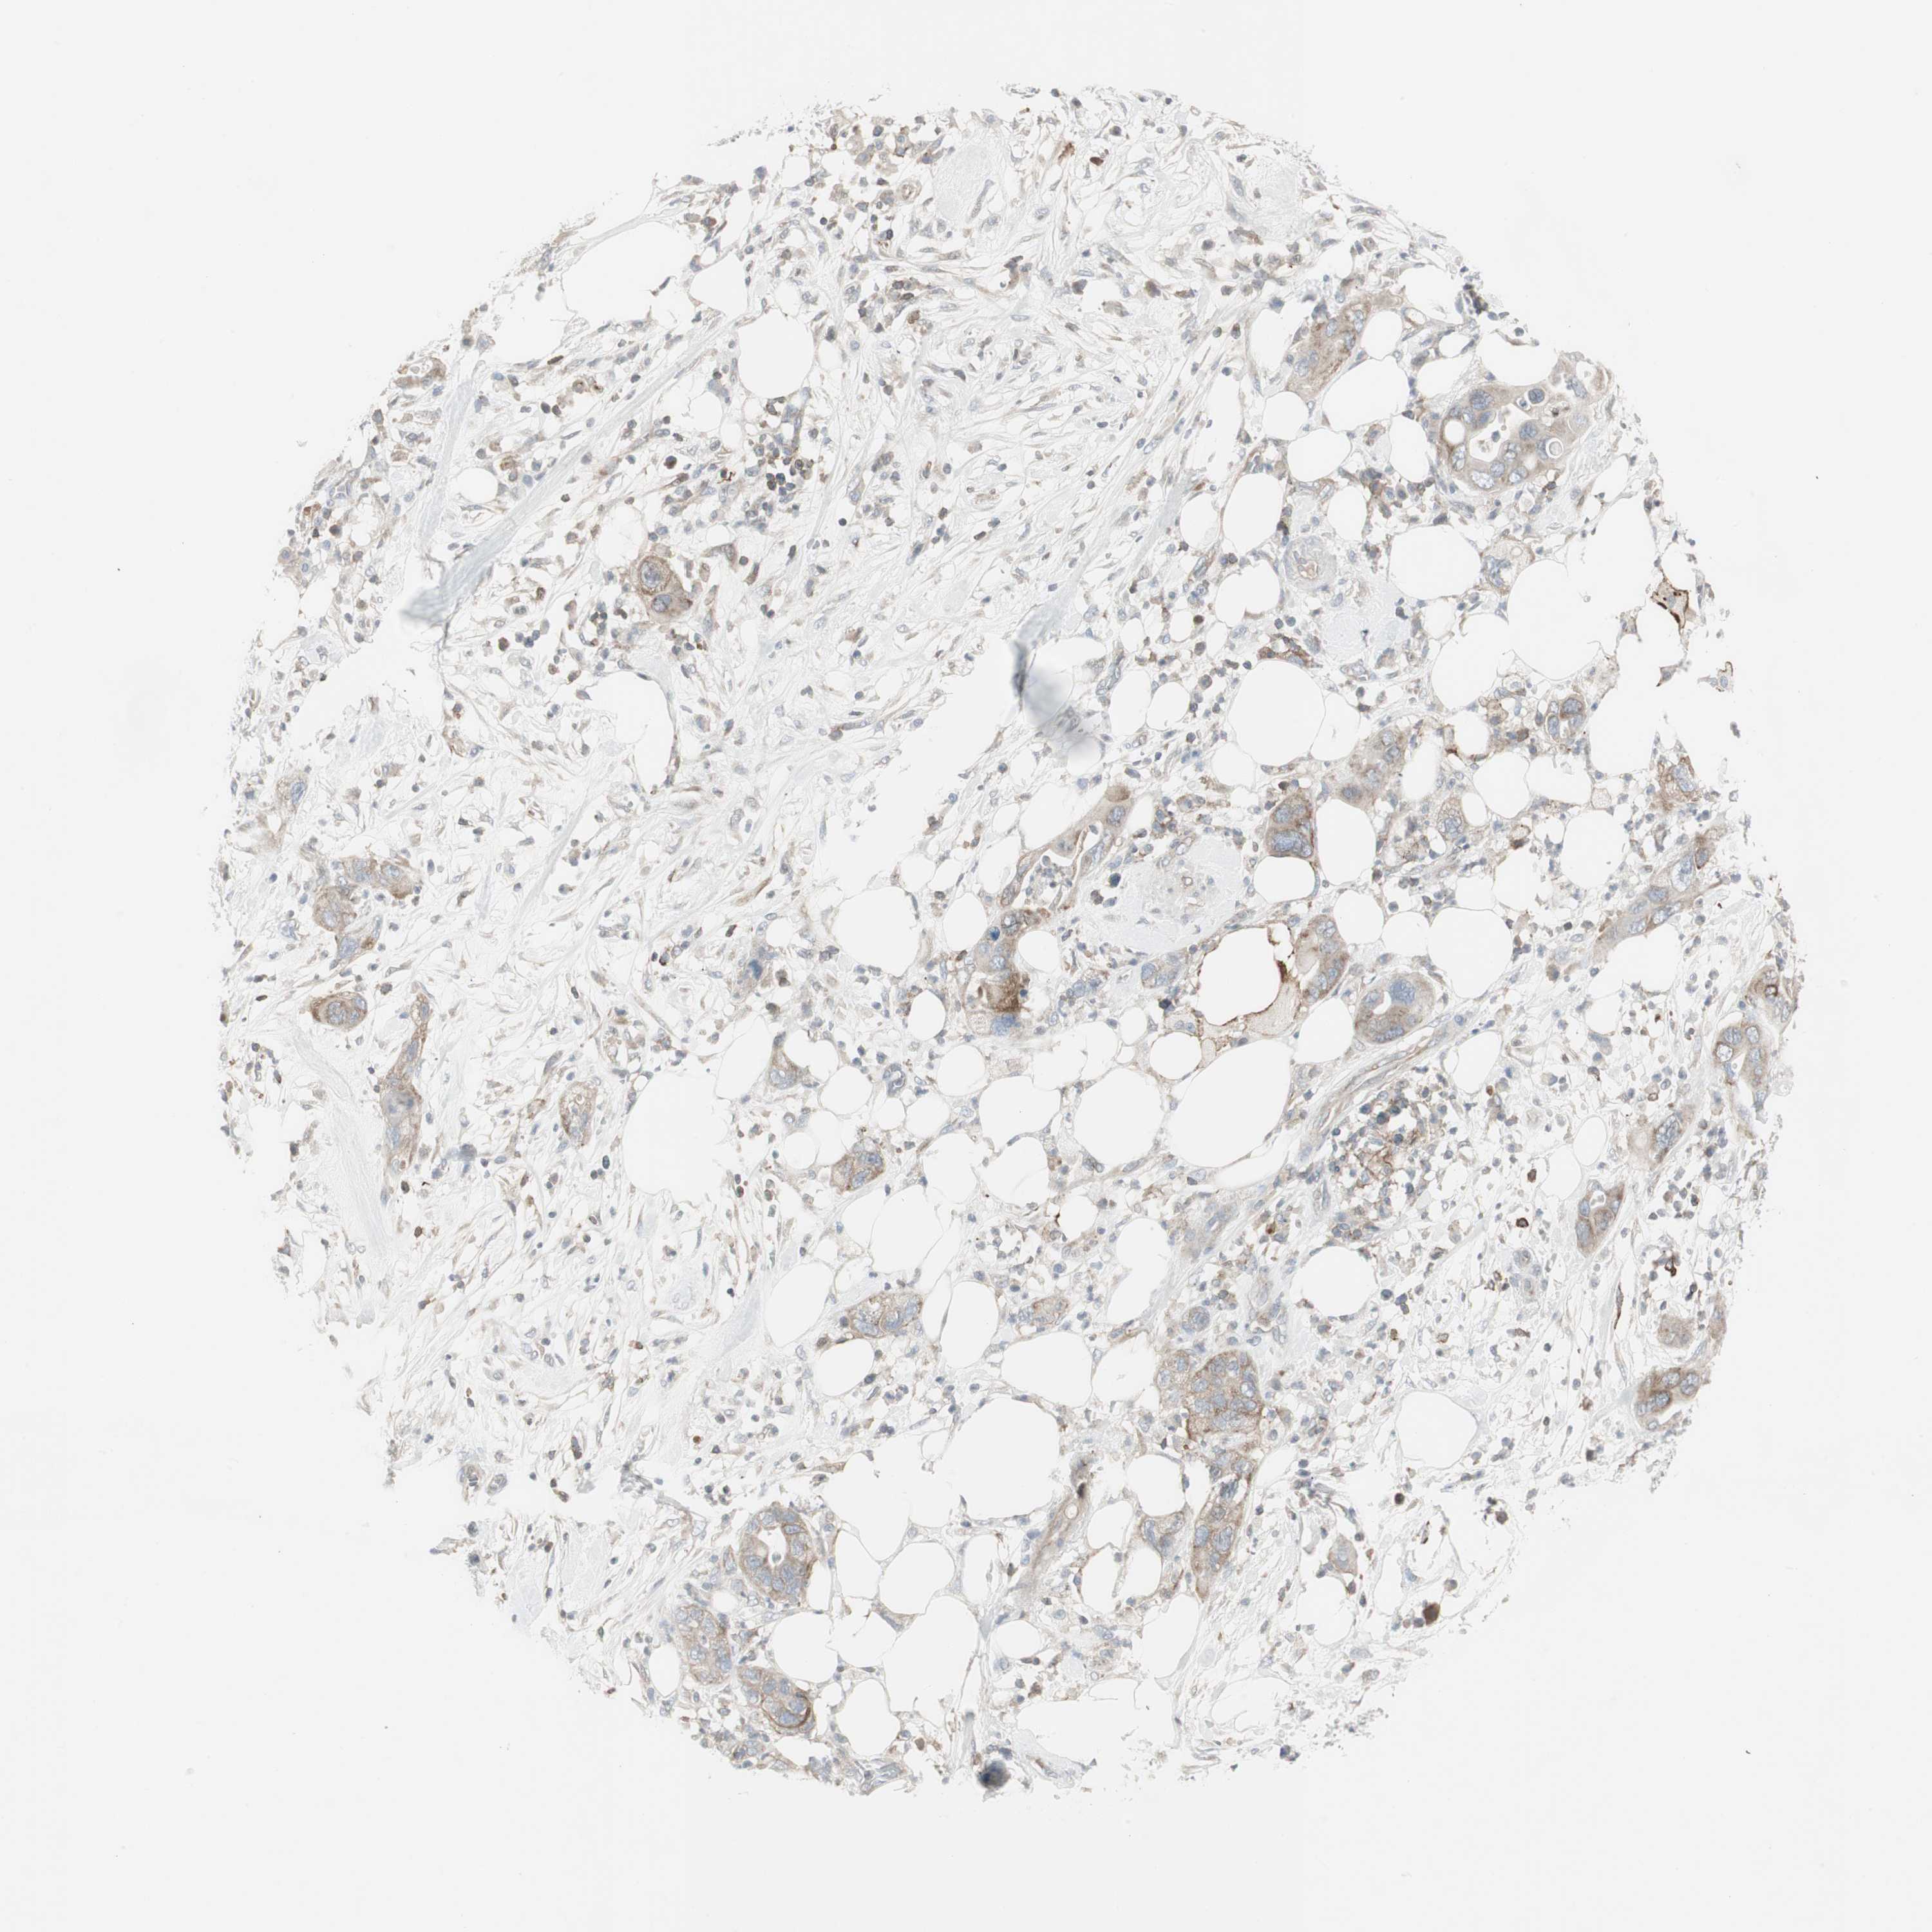

PANCREATIC CANCER - Protein expressioni

A mouse-over function shows sample information and annotation data. Click on an image to view it in a full screen mode. Samples can be filtered based on level of antibody staining by selecting one or several of the following categories: high, medium, low and not detected. The assay and annotation is described here.

Note that samples used for immunohistochemistry by the Human Protein Atlas do not correspond to samples in the TCGA dataset.

Antibody stainingi

Antibody staining in the annotated cell types in the current human tissue is reported as not detected, low, medium, or high, based on conventional immunohistochemistry profiling in selected tissues. This score is based on the combination of the staining intensity and fraction of stained cells.

Each image is clickable and will lead to virtual microscopy that enables deeper exploration of all samples and also displays staining intensity scores, fraction scores and subcellular localization as well as patient and tissue information for each sample.

Antibody HPA008476

Staining

High

Medium

Low

Not detected

Intensity

Strong

Moderate

Weak

Negative

Quantity

>75%

75%-25%

<25%

None

Location

Nuclear

Cytoplasmic/membranous

Cytoplasmic/membranous,nuclear

Adenocarcinoma, NOS